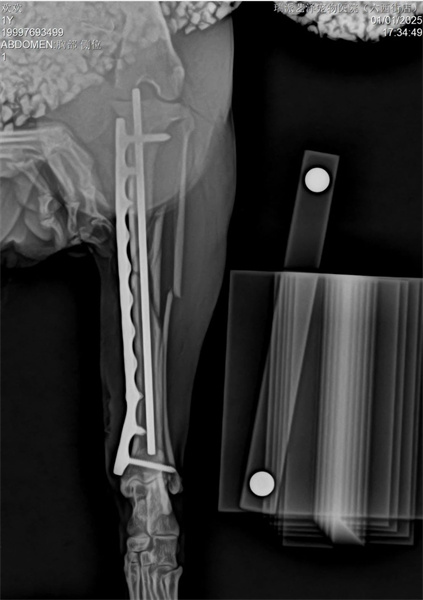

The lateral approach is used for the transverse fracture of the right humeral shaft, with full open contact for fixation of the head side and lateral dual Bone Plates. The transverse fracture plate hole is reduced with compression screws on the head side bone plate.

As it is a PRCL locking bone plate system, strive for perfect bone plate shaping, but do not deliberately pursue absolute shaping perfection

The tibia adopts the medial MIPO surgical approach to protect soft tissue as much as possible, and is fixed using intramedullary nails and bridging bone plates.

The tibia adopts PRCL8mm bone plate and 2.5mm needle, ensuring that there are at least two screws at the proximal and distal ends